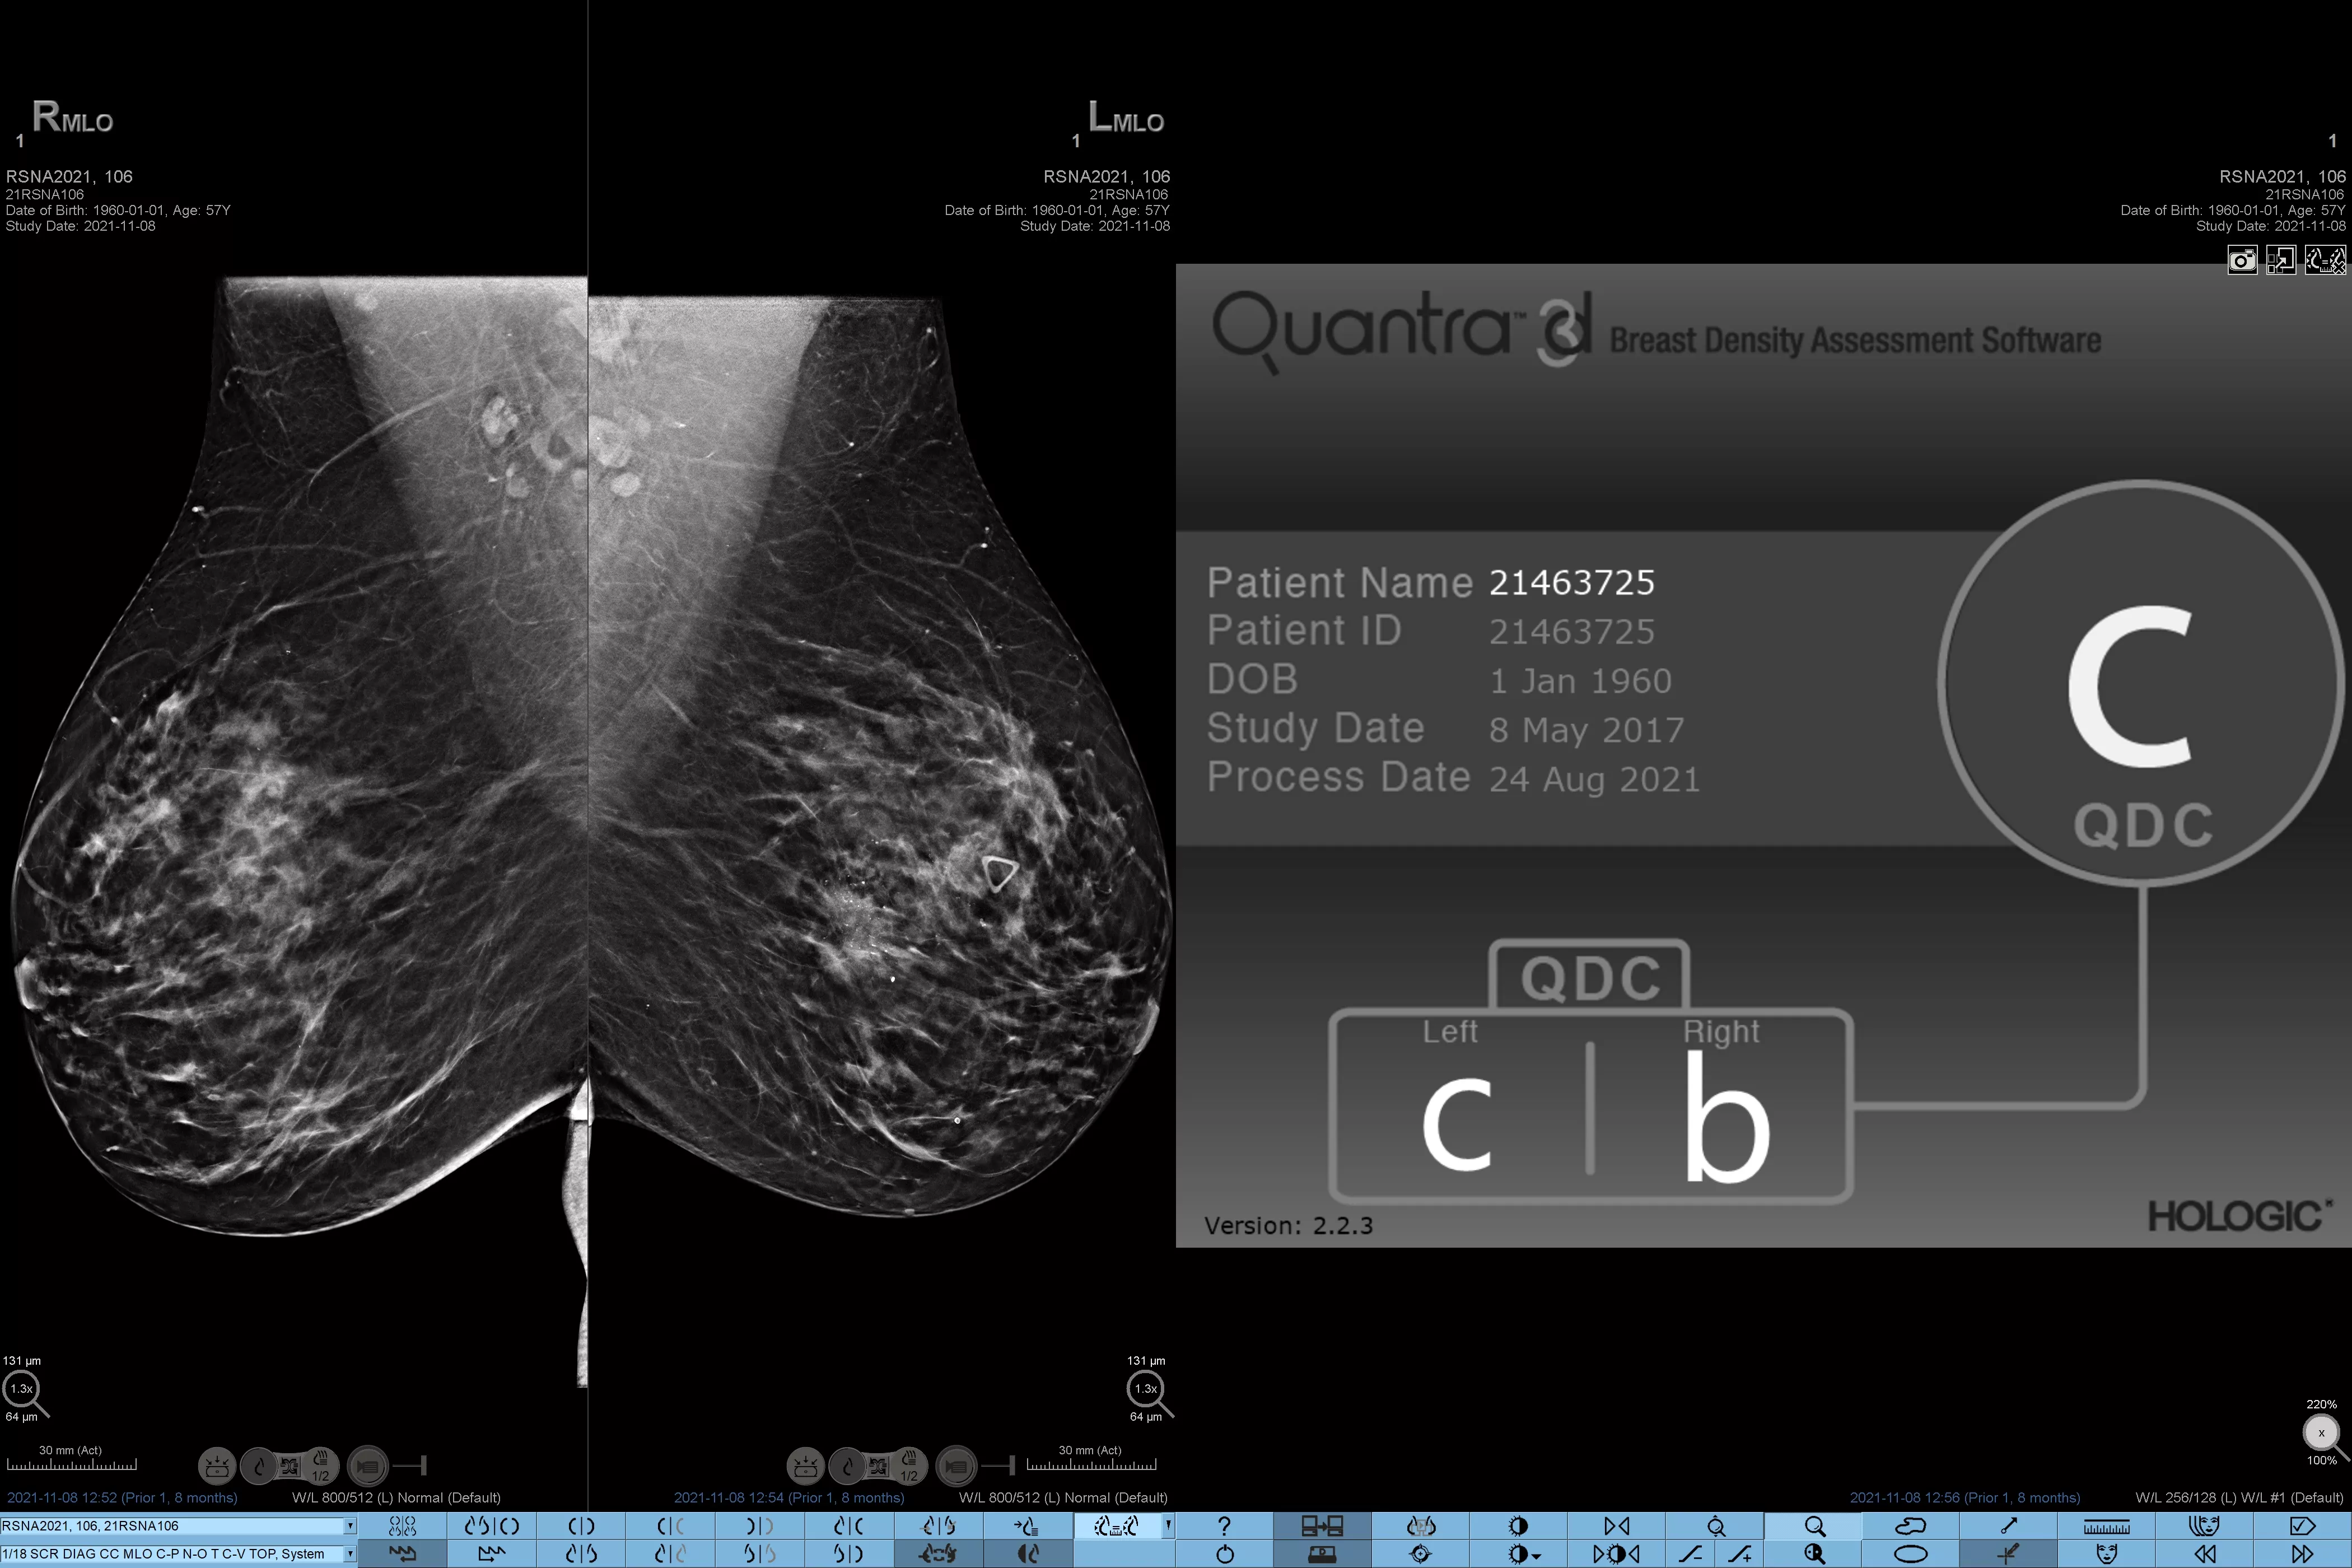

Higher breast density is known to increase a woman’s risk for breast cancer.1 The need for accurate, unbiased analysis is therefore critical. Powered by machine learning, Quantra technology software analyses both 2D™ and tomosynthesis images for distribution and texture of parenchymal tissue. It categorises breasts in four breast composition categories consistent with guidance from the American College of Radiology (ACR) BI-RADS Atlas 5th Edition.2

Objective machine learning algorithm that assigns breast density category based on analysis of breast tissue texture and patterns.

Quantra software’s unbiased algorithm analyse both 2D and tomosynthesis images to support your analysis by:

• Overcoming subjectivity in visual assessment, providing more consistent, and more reliable scoring.*

• Elevating the standard of care and standardises reporting.

• Facilitating patient management protocols for supplemental imaging.